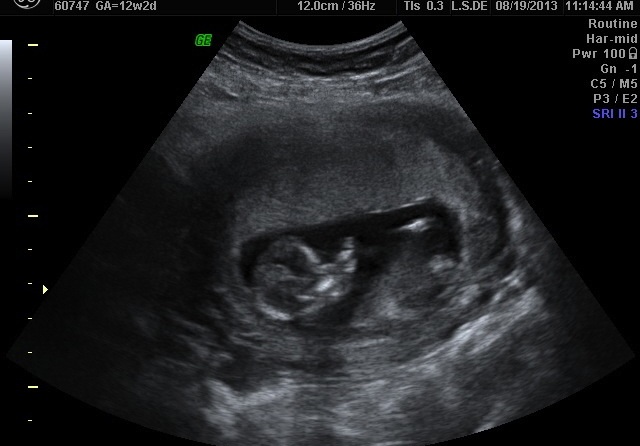

12+2 us, no clues :(

Hi ladies, it's been a while since I last posted here, wasn't very active though. The thing is that I got a surprise pregnancy the month before was going to start my sway and i've been having a hard time because of that, kind of depressed because i think i wasted my last chance to have a girl. Anyway, i had my nt scan today, but i can't see any clues in the pictures, i have more if you need but i think this is the "best". Can you make a guess? Thank you!!

Thanks for guessing! I thought I saw the nub during the us. She gave us an optional cd for 30$ with what I was thinking was the video but I realized at home that it's just a bunch of pictures :-(. And I can't see the nub in any of them.

Do you see a nub or it's the skull what makes you think girl?

Can you see anything in this other picture? Thanks!